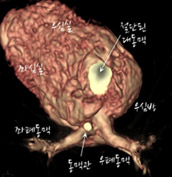

- 위에서 본 모습

수술 전에 대동맥이 심장 앞쪽에서 기시하는 것을 관찰할 수 있습니다. 수술 후 대동맥 자체가 후방으로 이동했고 폐동맥으로 lecompte maneuver를 해서 대동맥 앞으로 옮기고 좌,우폐동맥이 팔을 벌린 모양을 하고 있습니다. 폐동맥이 이전의 대동맥 자리에 위치해 전방의 흉골에 덜 눌리는 모양입니다.

[사진6] 수술 전 -

[사진7] 수술 후